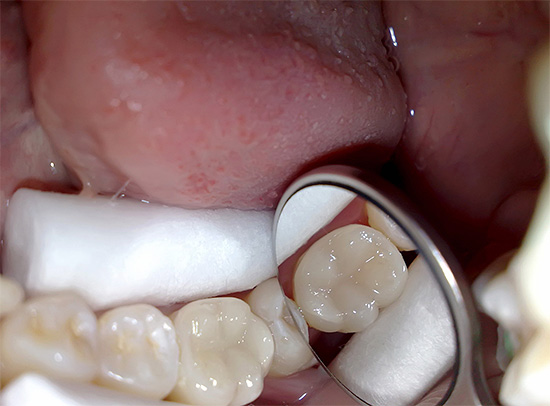

Foto dei residui di polpa rimossi dal canale radicolare del dente:

Per gli stessi motivi, è impossibile eseguire l'amputazione vitale preservando solo la polpa della radice, poiché è quasi sempre già coinvolta nei processi di necrosi.